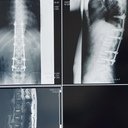

そんな中、去年の11月にマンションの5Fから転落してしまい腰椎2本破裂骨折、胸椎2本圧迫骨折をし

現在は背中に30cmほどのチタンが背骨にそって入れられていて、それを止める為のボルトスクリューが計10本入っている状態で、背中を曲げたり反ったり捻ったりすることができません。

かなり大幅切開の手術をした影響で、腰全体が現在も痺れていて右足の付け根にはほとんど力が入りません。今でも杖を使って歩くのがやっとの状態で、杖を使わず立ってるのは10分や20分が限界で少しでも無理をすると夜には激痛に襲われます。

今年の11月に再手術予定で、理学療法士の方からはそれからがリハビリの本番と言われています。